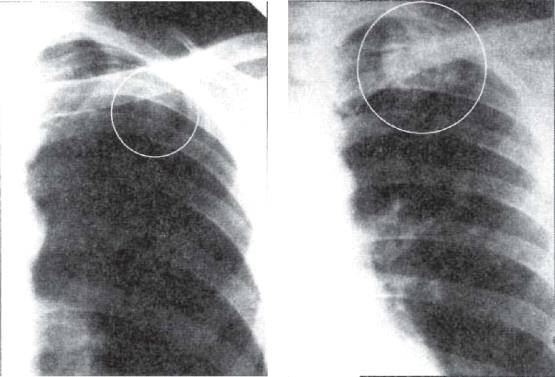

Иллюстрации по теме очагового и инфильтративного туберкулеза

Раздел: Фотодневник открытий